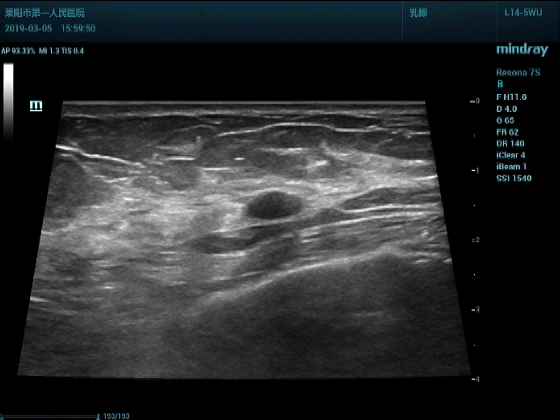

超声入门贴994--乳腺纤维瘤(弹性成像)